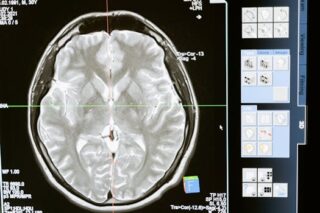

Understanding Cat Scans

A cat scan, short for computed tomography scan, is an imaging procedure that combines a series of X-ray images taken from different angles around the body. Using computer processing, these images produce cross-sectional pictures, considered more detailed compared to standard X-rays. These scans can reveal the inner details of various body parts, including organs, bones, soft tissues, and blood vessels.

One external trusted source explains cat scans are particularly beneficial because they provide much more information than a regular X-ray. This precision and clarity enable healthcare practitioners to pinpoint issues that might otherwise go unnoticed.